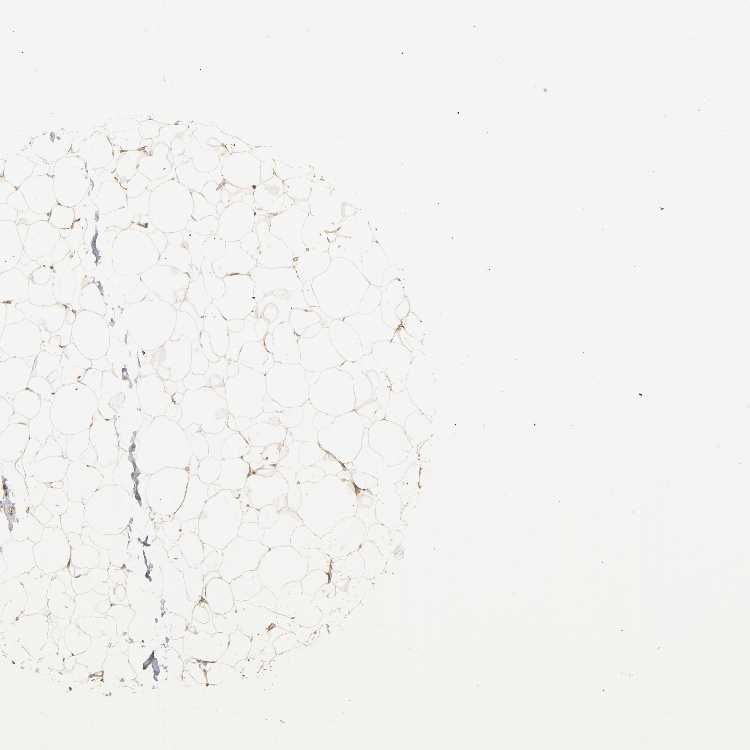

BREAST - Antibody stainingi

Antibody staining in the annotated cell types in the current human tissue is reported as not detected, low, medium, or high, based on conventional immunohistochemistry profiling in selected tissues. This score is based on the combination of the staining intensity and fraction of stained cells.

Each image is clickable and will lead to virtual microscopy that enables deeper exploration of all samples and also displays staining intensity scores, fraction scores and subcellular localization as well as patient and tissue information for each sample.

Antibody CAB005052

Adipocytes Medium

Glandular cells Low

Myoepithelial cells Not detected